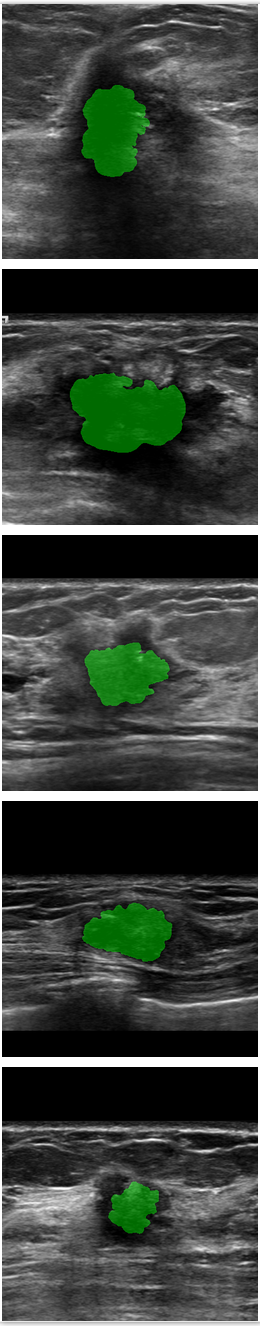

Refer to caption

Figure 6: Comparison of SPCGAN and other segmentation methods of benign lesions. (a) shows original image of benign lesions, (b) shows the manual annotation, (c) shows the result of SPCGAN ,(d), (e) and (f) show results from ResNet, Mask R-CNN and level set.

Fig.6 displays the segmentation results of our SPCGAN, FCN(ResNet), Mask R-CNN and the level set method from benign lesions. Compared with the FCN(ResNet) (d), Mask R-CNN (e) and the level set (f) method, the results of our SPCGAN (c) show good agreements with the manual contours of the lesions. The segmentations from SPCGAN are very close to manual segmentations.